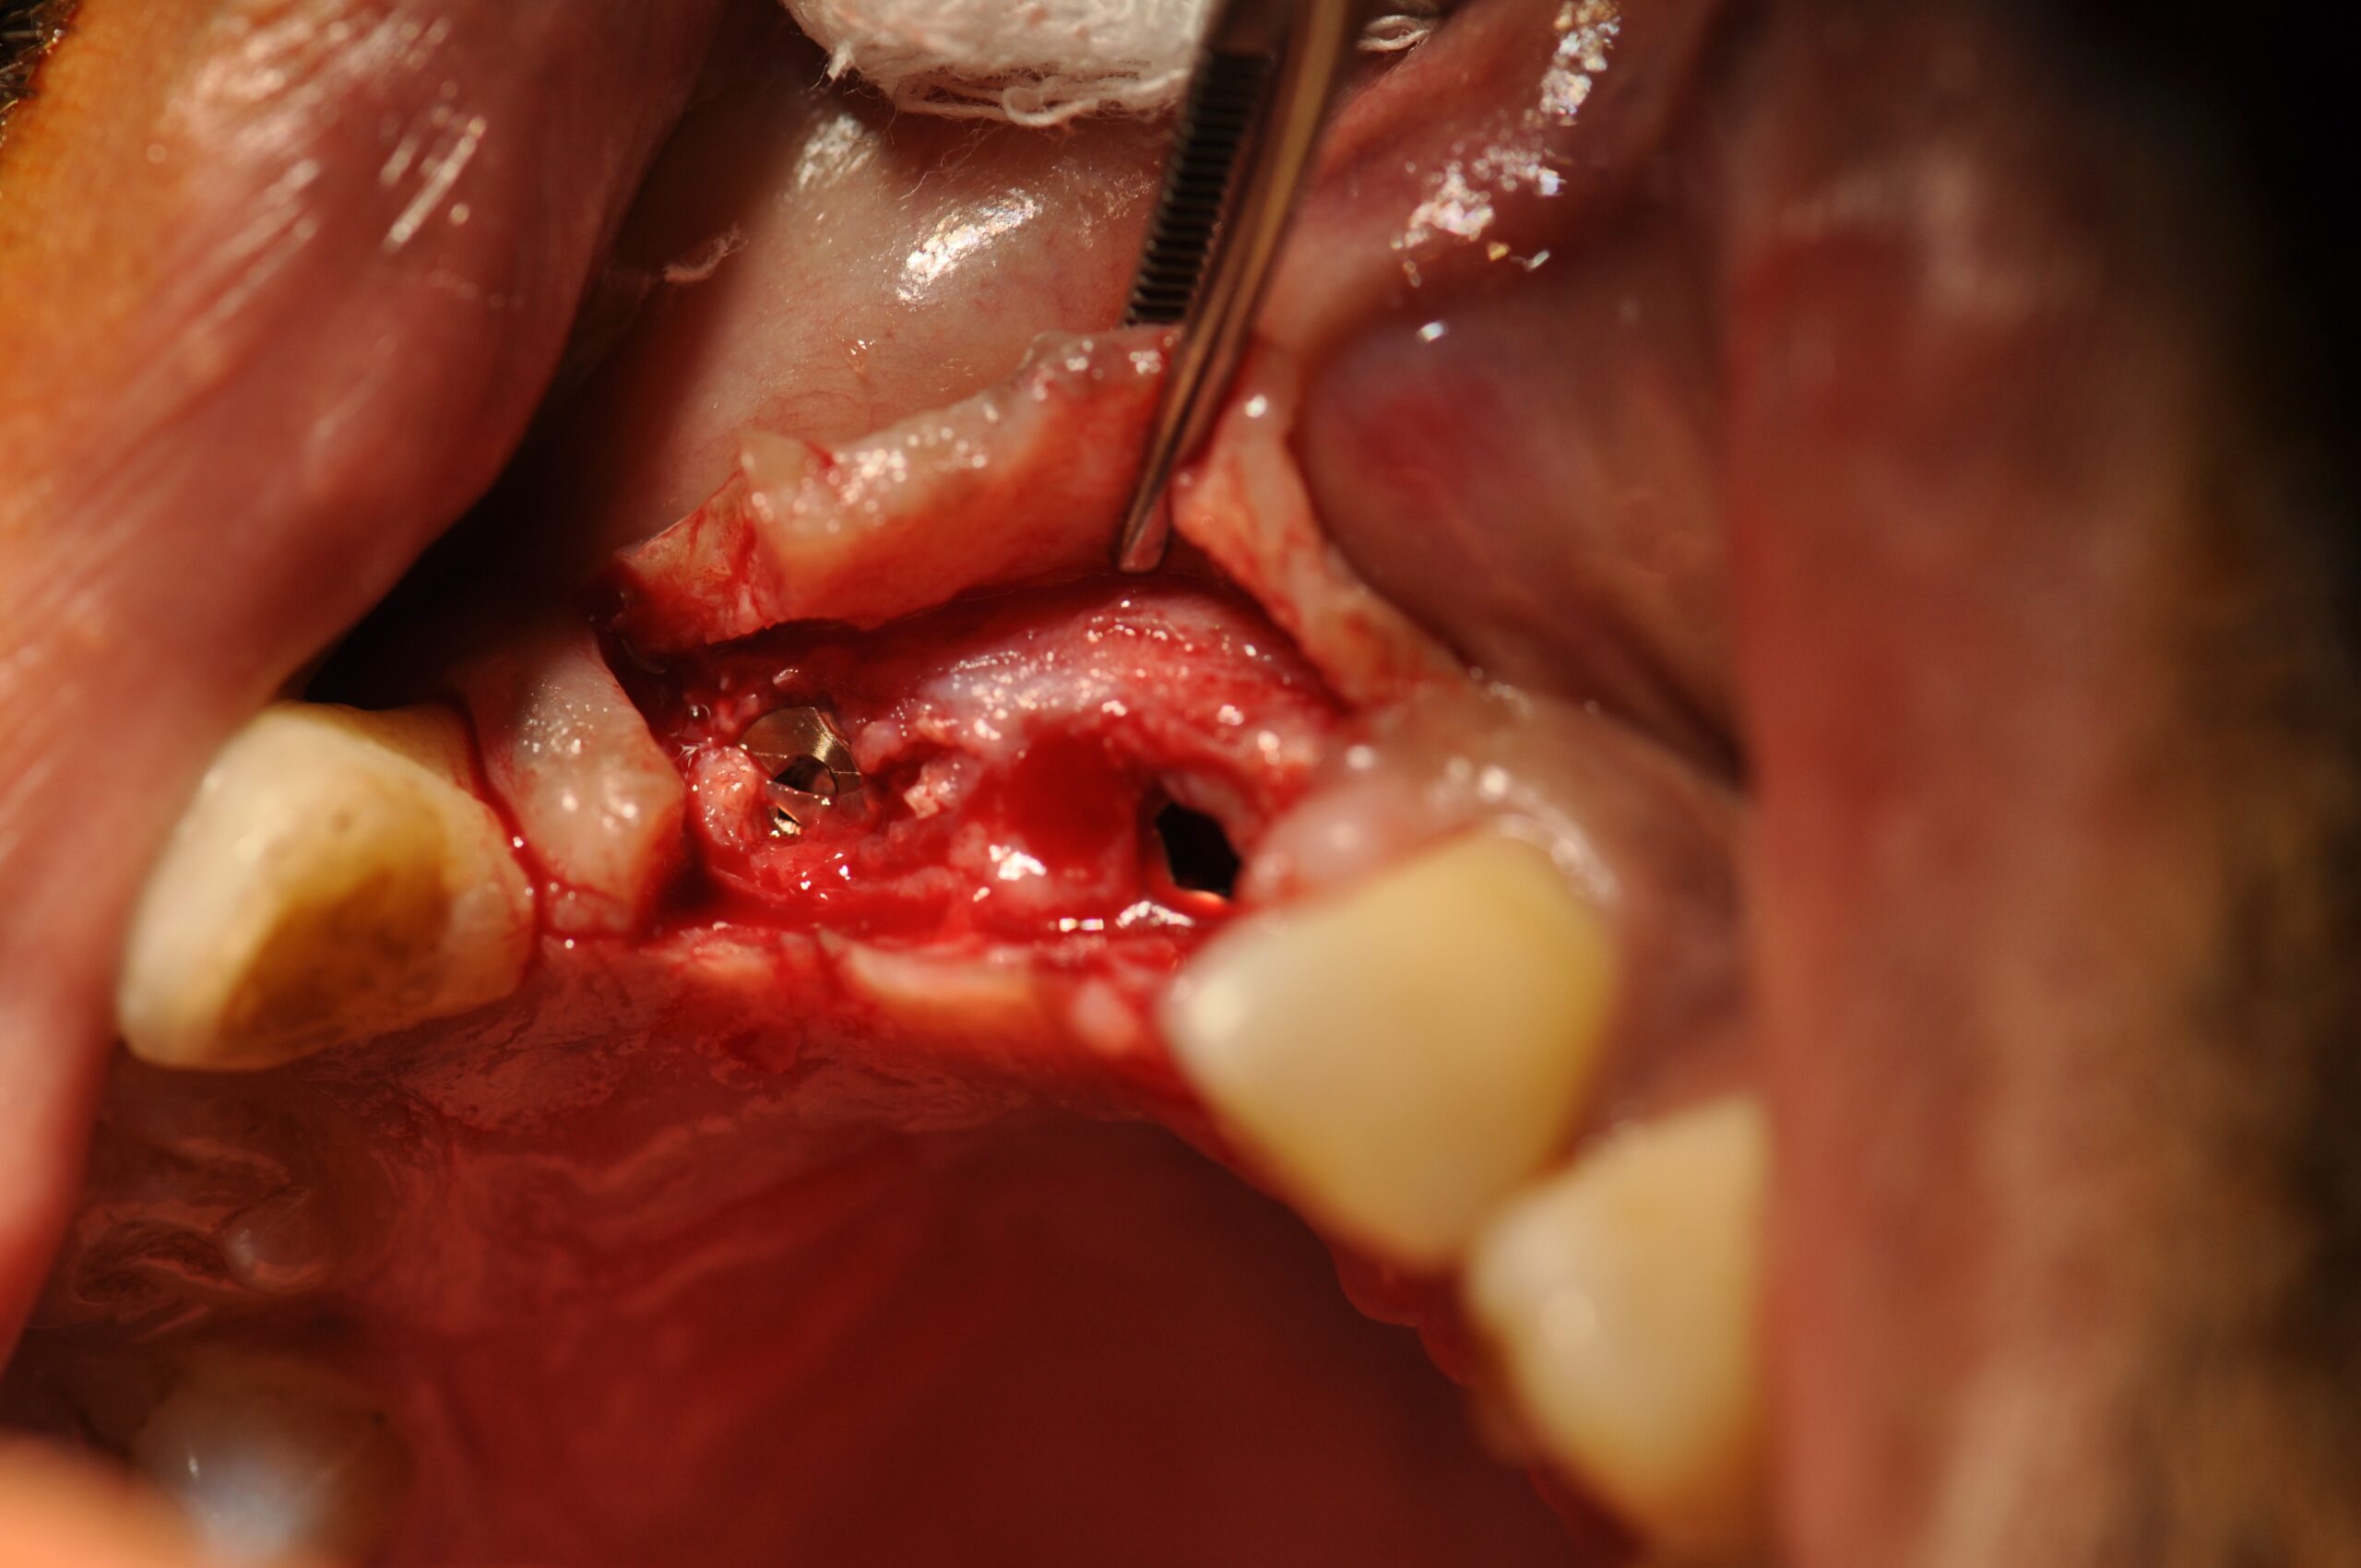

→ Pose du ou des implants

Durant cette étape, le praticien pose les implants dentaires pour remplacer les racines manquantes. À l’issue de cette intervention, vous sentirez des implants couverts par la gencive, et qu’ils sont mis en “nourrice” : cela permet à l’os de cicatriser autour des implants.

L’implant dentaire est placé dans la mâchoire sous anesthésie locale dans la majorité des cas, parfois sous anesthésie générale.